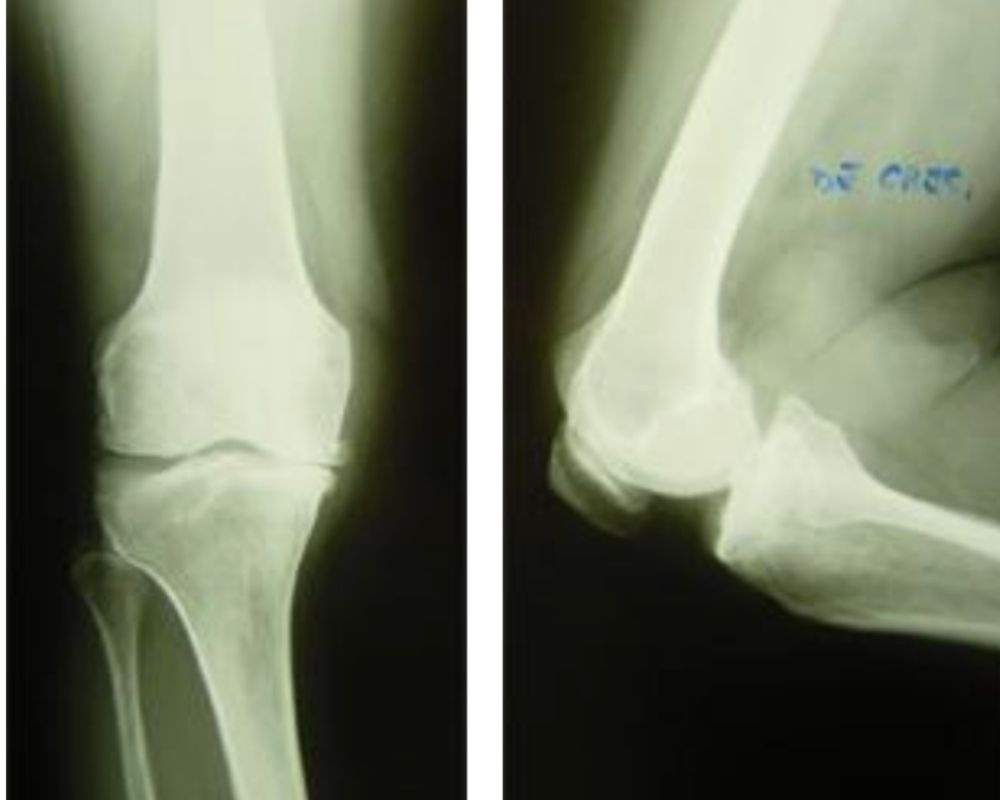

Rx Preoperatoria

Rx postoperatoria

L’artrosi del ginocchio (gonartrosi) può manifestarsi con usura della cartilagine associata alla formazione di osteofiti (per iperproduzione di osso ai margini articolari) e riassorbimento dell’osso subcondrale con formazione di geodi.

Nel tempo, tutti questi fenomeni portano a una progressiva deformazione dell’articolazione con limitazioni della sua funzionalità tali da compromettere la mobilità e la qualità di vita.